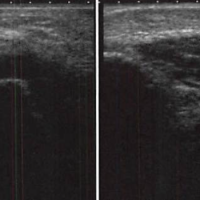

野球肘を共に克服しましょう

おはようございます。 四ツ谷接骨院の藤本です。 本日は、野球選手にとって 天敵の「外側型の野球肘」についてお話したいと思います。 ところで野球のみならず学生スポーツの最大幸せは何でしょうか? 勝つこと! 健 …